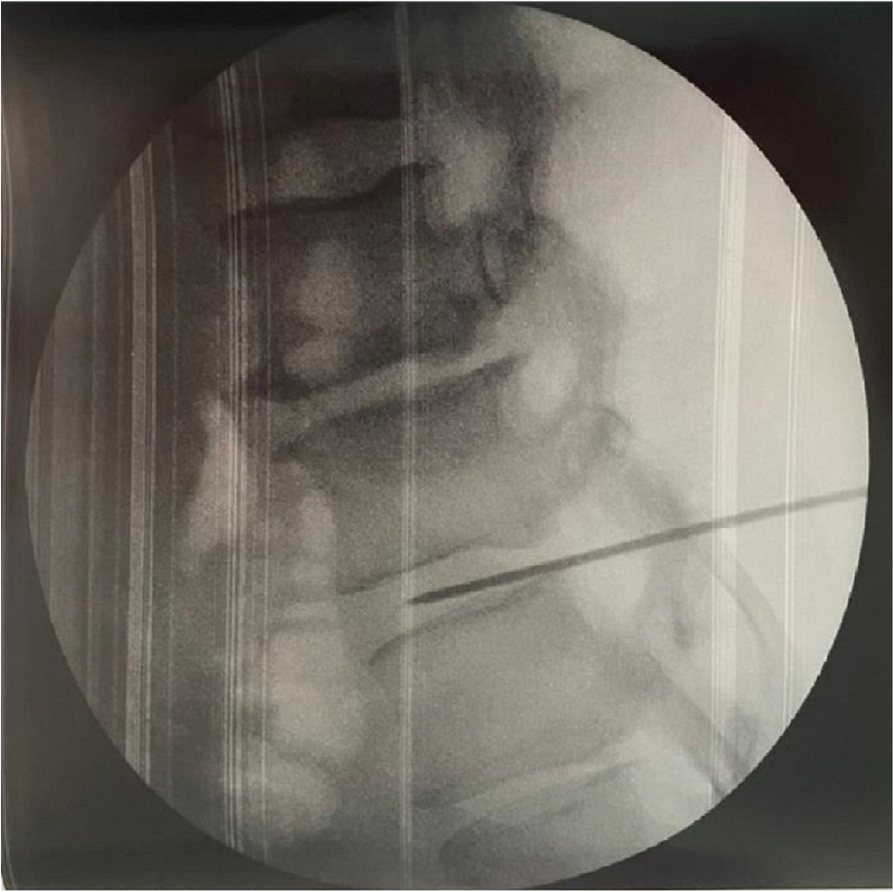

A few hours after the admission in ICU he reported a blunt abdominal pain, mainly on the right side, nausea and the exams showed increased amylase levels, urologists excluded any surgical involvement of pancreatic tissue and suspected a transient sphincter of Oddi dysfunction [3]. After one night in ICU he was transferred to the urology ward due to his clinical stability, even though Amylase peaked at 2340 U/l. Two days later abdominal pain increased to severe, with characteristics of peritonism and increased inflammatory markers. An abdomen-thorax CT scan revealed acute pancreatitis (AP) (Figure 1) and he was transferred to ICU. He started a standard treatment for acute pancreatitis and antibiotic therapy [4].

On postoperative day nine, due to general deterioration of clinical conditions and further anemization that required blood transfusion, he underwent an emergency laparotomy, in which propofol was not used as an anesthetic drug, that found a completely necrotic pancreas. The following day he faced a multi organ failure (MOF) which rapidly led to death. Consent to publish the case report was accorded by the family.